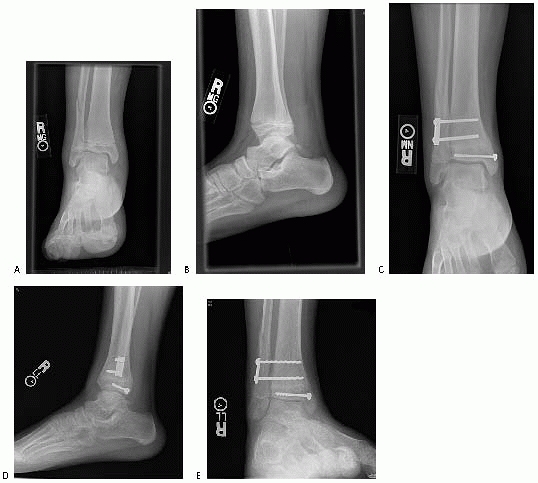

![]() |

FIGURE 26-16 Triplane with deltoid injury and syndesmosis widening with stress views. A,B. Injury films. C-E. Postoperative films.